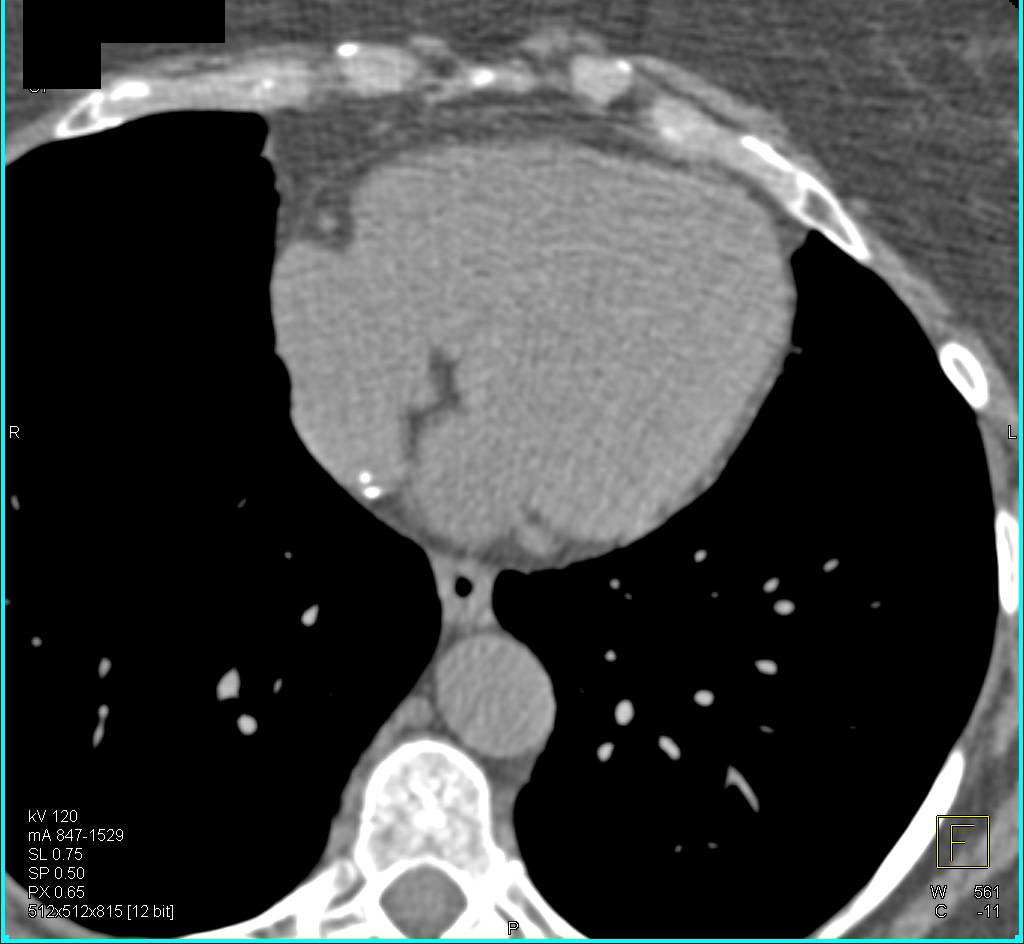

CTA with Occluded Superficial Femoral Artery (SFA)-Popliteal Artery Bypass Graft